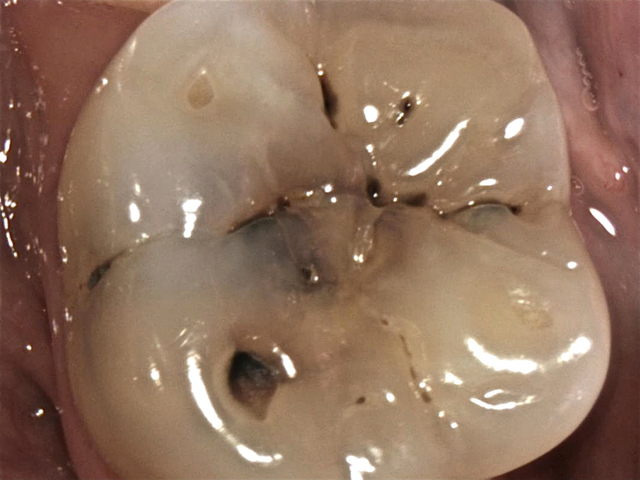

Karies in den Fissuren ... (Intraoralkamera)

Tiefe Fissurenkaries ... (Intraoralkamera)